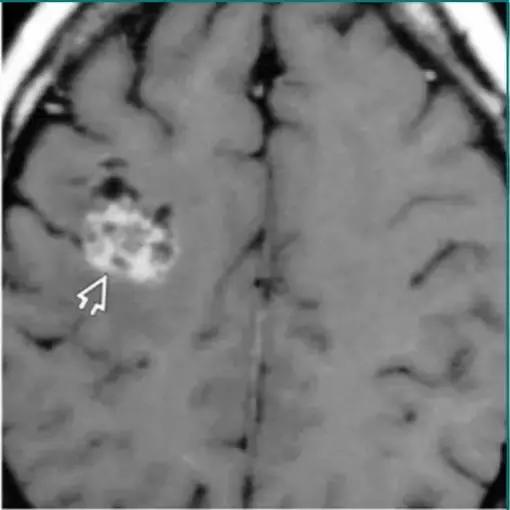

囊性转移